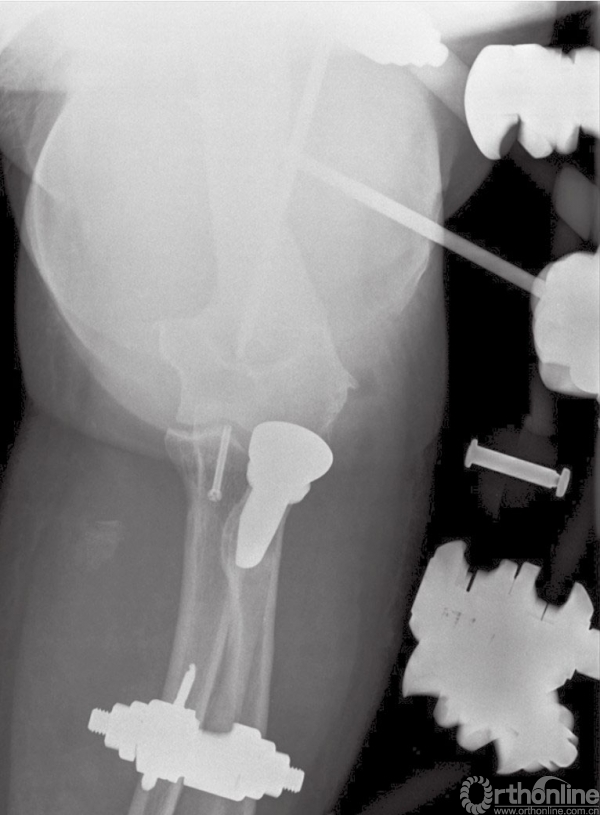

在内固定完成和韧带的损伤修复后,在手术台上验证患者肘关节的稳定性。如果发现肘关节稳定性不可靠或者存在再次脱位风险,建议使用铰链式外固定支架,这样可以使肘关节获得同轴心的稳定性,并可以使患者在术后早期活动。

对于没有合并并发症的患者,我们也倾向于术后使用铰链式外固定支架,以避免不可控的关节活动。使用外固定支架可以中和修复后骨折端及韧带复合体所受的应力,防止术后早期活动时发生再脱位及内固定失败。外固定支架一般使用6周(图12)。

图12 术后使用铰链式外固定支架,有利于术后软组织损伤恢复及早期活动